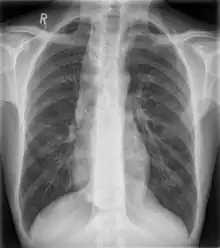

![]() Mediastinum anatomy. ![]() Some mediastinal structures on a chest radiograph.